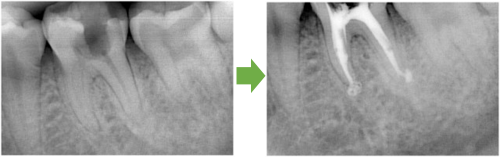

抜髄 右上の奥歯 川口の歯科 歯医者 さかえ歯科クリニック

2014年12月16日